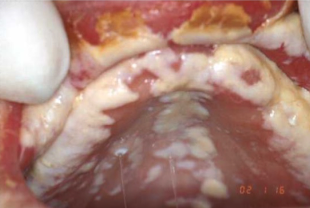

what classification of oral candidosis is shown here?

pseudomembranous

chronic hyperplastic

angular chelitis